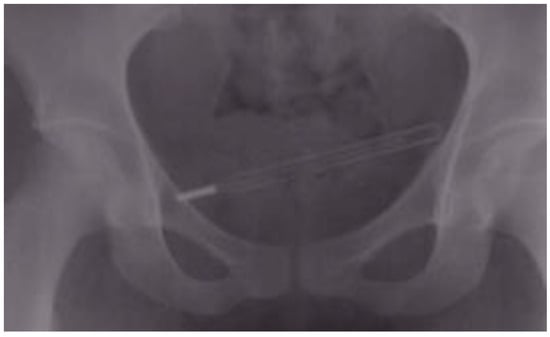

| 1 | 34 | M | wire | urinary bladder | unknown | unknown | hematuria | cystotomy |

| 4 | 63 | M | hairpin | urinary bladder | sexual stimulation | <24 h | none | cystotomy |